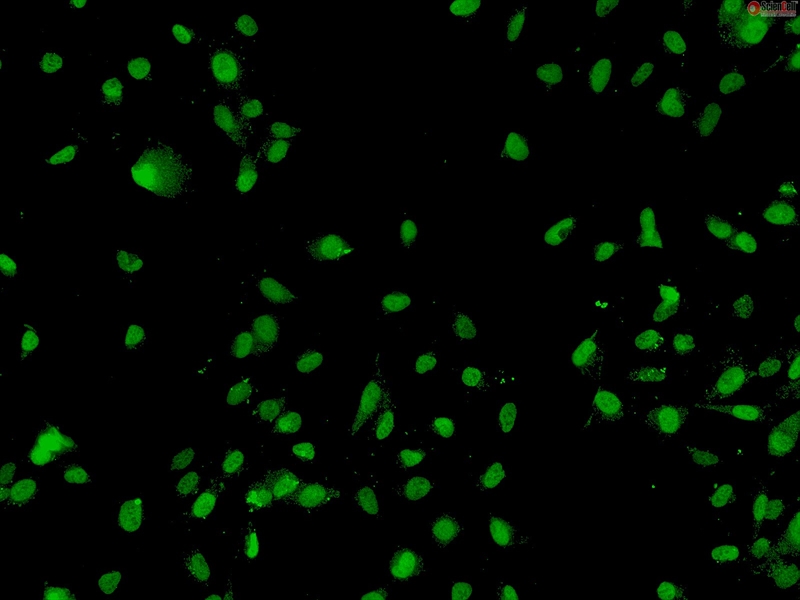

Human Sertoli Cells, Passage 1

Cryopreserved Primary Cells, Single Donor

Sertoli Cells (SerC) are essential for testicular development, spermatogenesis, and formation of the blood-testis barrier. SerC limit the passage of substances such as hormones and nutrients to the adluminal compartment of the seminiferous tubules. In addition to forming the blood-testis barrier, SerC also provide the main structural support for the seminiferous tubules and protect the germ cells from the immune system. Aberrant SerC proliferation can contribute to the development of male reproductive disorders such as testicular germ-cell cancer, cryptorchidism, hypospadias, and low sperm count. SerC proliferation is in part controlled by follicle-stimulating hormone (FSH) and thyroid hormone (TH), where FSH drives proliferation and TH promotes a more quiescent state. Cultured Human SerC are a useful in vitro model to better understand testicular dysgenesis syndrome and to develop treatments for male reproductive disorders. (SC4520)